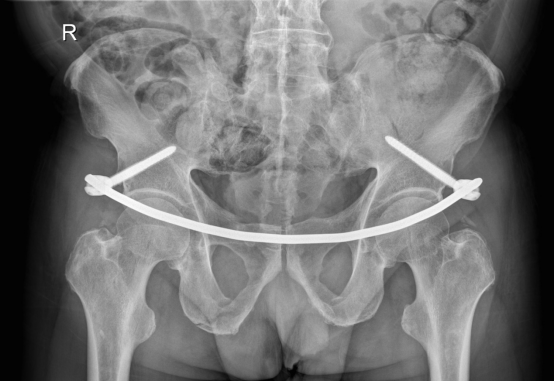

目前骨盆前环骨折的固定方式主要有四种:钢板、螺钉、外固定支架、内固定支架(即Infix技术)。由于前三种手术技术存在一定局限性,学界一直在寻找一种更加安全可靠、操作简单的骨盆前环骨折固定技术。

2009年:Kuttner研发了一种基于经皮下骨盆前环内固定技术(internalfixator, INFIX),用于耻骨联合分离的复位与固定,后续所有24例患者,术后复查复位均良好。

2012年:Vaidya详细阐述并明确提出了Infix的观念:Internal fixator适用于前环损伤的骨盆骨折,尤其是肥胖、伴有膀胱损伤的患者。

该手术在皮下操作,在超髋臼区进行固定稳固,具有力臂短、把持力强、操作简单、创伤小、容易取出、允许早期锻炼及负重、不需要考虑血管神经等优点,更符合BO原则。